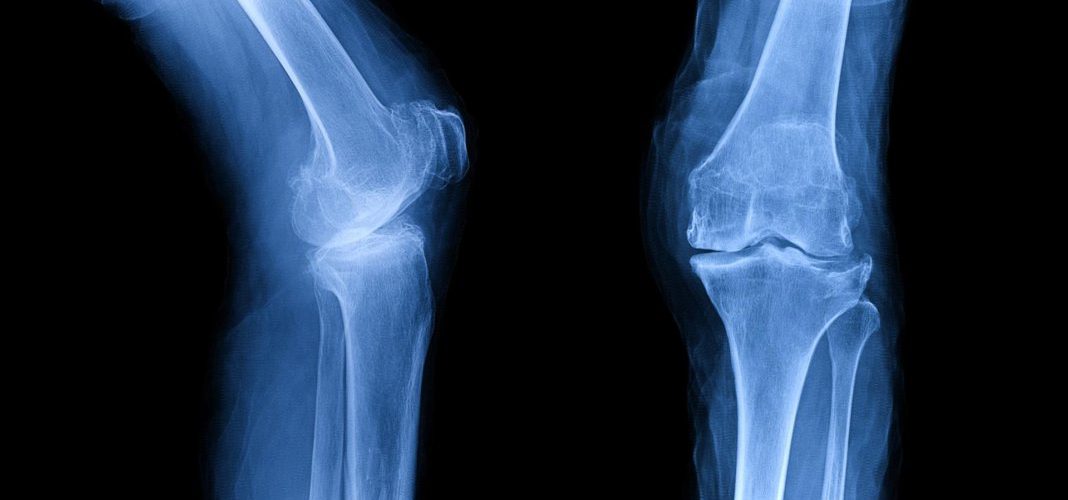

אבחון של אוסטאוארטריטיס של הברך

לעיתים במהלך התהליך יידרשו בדיקות נוספות בכדי לאפשר אבחון, לדוגמת צילומי רנטגן אשר יעידו על נזק שנגרם לעצם ולסחוס, בדיקת MRI במידה וצילומי הרנטגן לא הניבו תוצאה ברורה וחד משמעית, ובדיקות דם שיאפשרו לשלול גורמים אחרים לכאבים בברך.